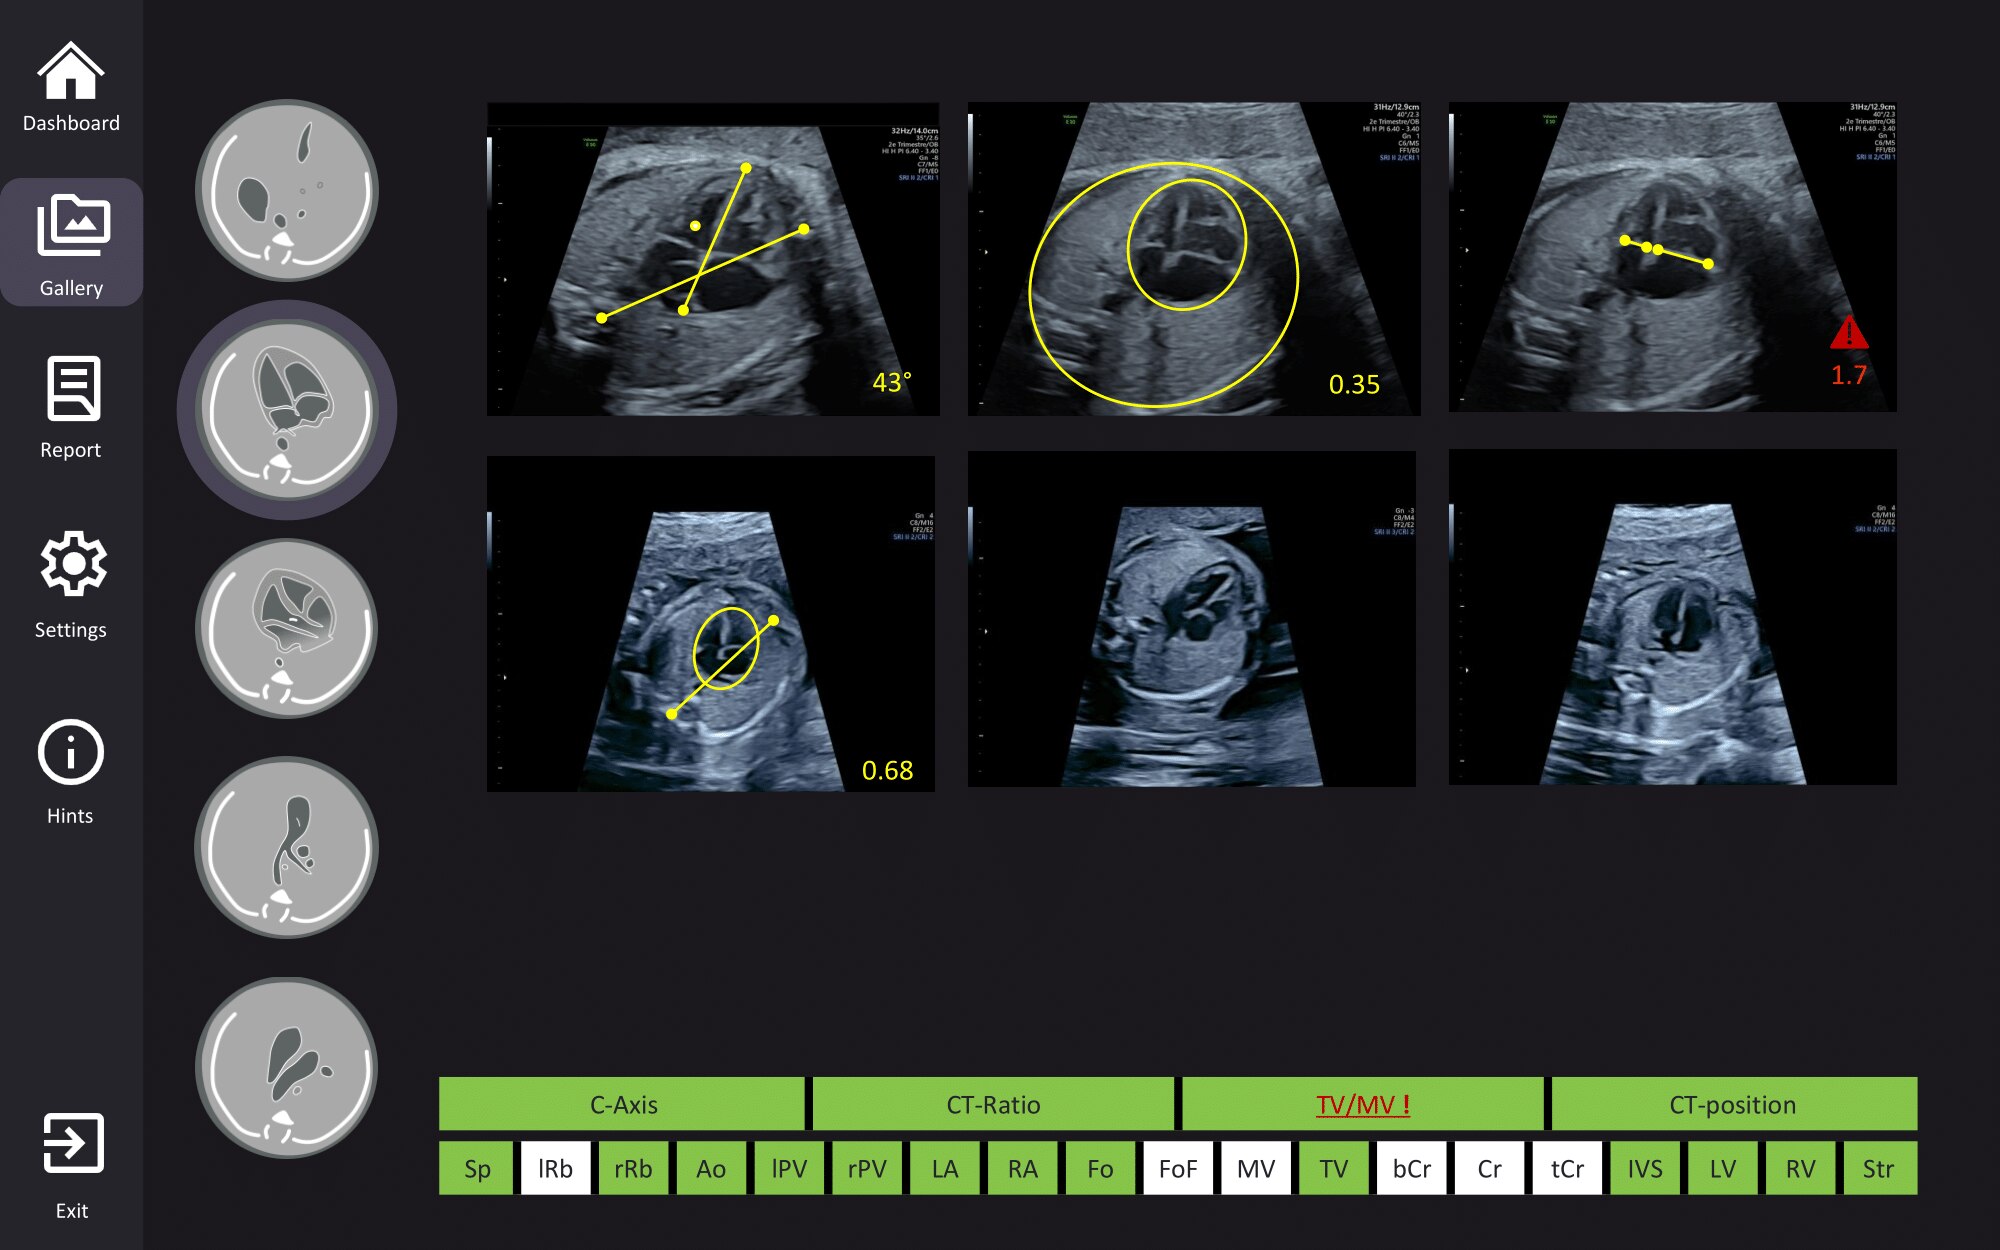

Fetoly

AI screening assistant for fetal heart and brain

Fetoly is the first real-time AI solution for fetal ultrasound, helping to ensure a complete and standardized examination. Integrating with most ultrasound systems, it provides instant feedback to help diagnostic confidence and help improve pregnancy outcomes.

• Instantly detects over 100 key fetal structures

• Automatic freeze and view selection

• Real-time ratios supporting the detection of pathologies